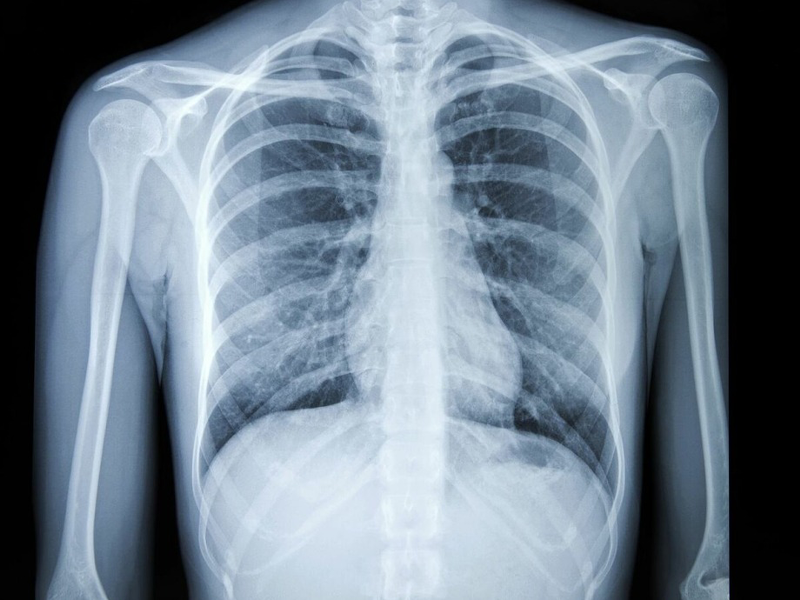

Bệnh nhân Đỗ Duy Bình, 55 tuổi ở Việt Trì, Phú Thọ cho biết, trong suốt 10 ngày trước khi đến viện, ông thường xuyên ho khan. Dù đã đi nhiều cơ sở y tế khám nhưng không tìm ra bệnh. Khi đến BV đa khoa tỉnh Phú Thọ, ông Bình được bác sĩ thông báo phát hiện tổn thương ở đỉnh phổi phải.

Làm thêm sinh thiết, bác sĩ kết luận ông mắc ung thư phổi biểu mô không tế bào nhỏ, chỉ định phẫu thuật cắt u, cắt thùy trên phổi phải, nạo vét hạch.